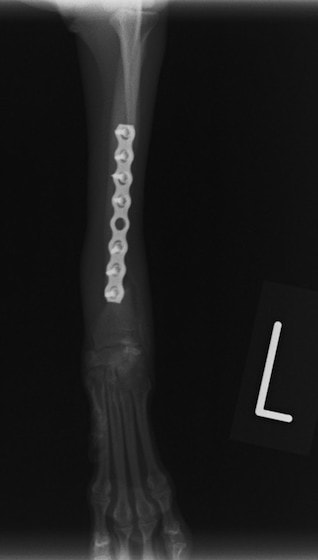

トイプードル 右遠位橈尺骨短斜骨折のALPSによる内固定

当院ではAdvanced Locking plate system(ALPS)と、Locking compression plate system(LCPS)という骨接合法で骨折症例の治療を行っています。

Advanced Locking Plate System

従来型のプレートのように広い面積で骨と接するプレートを用いて固定を行った場合、プレート下の骨はプレートとの接触面において血行が絶たれ壊死し、それがリモデリングされると骨密度が低下する。この骨密度の低下防ぐために、骨折部局所への血行を温存することの重要性が近年改めて認識されるようになってきている。Advaed Locking Plate System (ALPS)は従来型のプレートシステムの欠点を改良し、より使いやすく、より骨への血行を阻害しないようにというコンセプトで作られた。